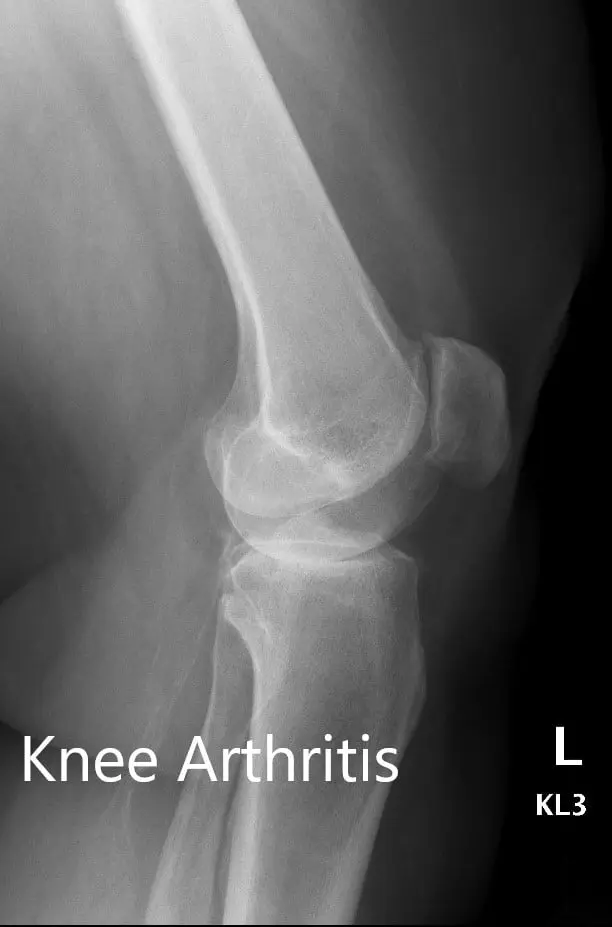

There was no distal neurological deficit and the bilateral distal pulses were comparable. The bilateral lower extremity superficial and deep tendon reflexes were positive and comparable. Imaging revealed osteoarthritis of bilateral knees (left > right). Smoking cessation education was given to the patient.

Preoperative X-ray showing the AP and lateral views of the left knee